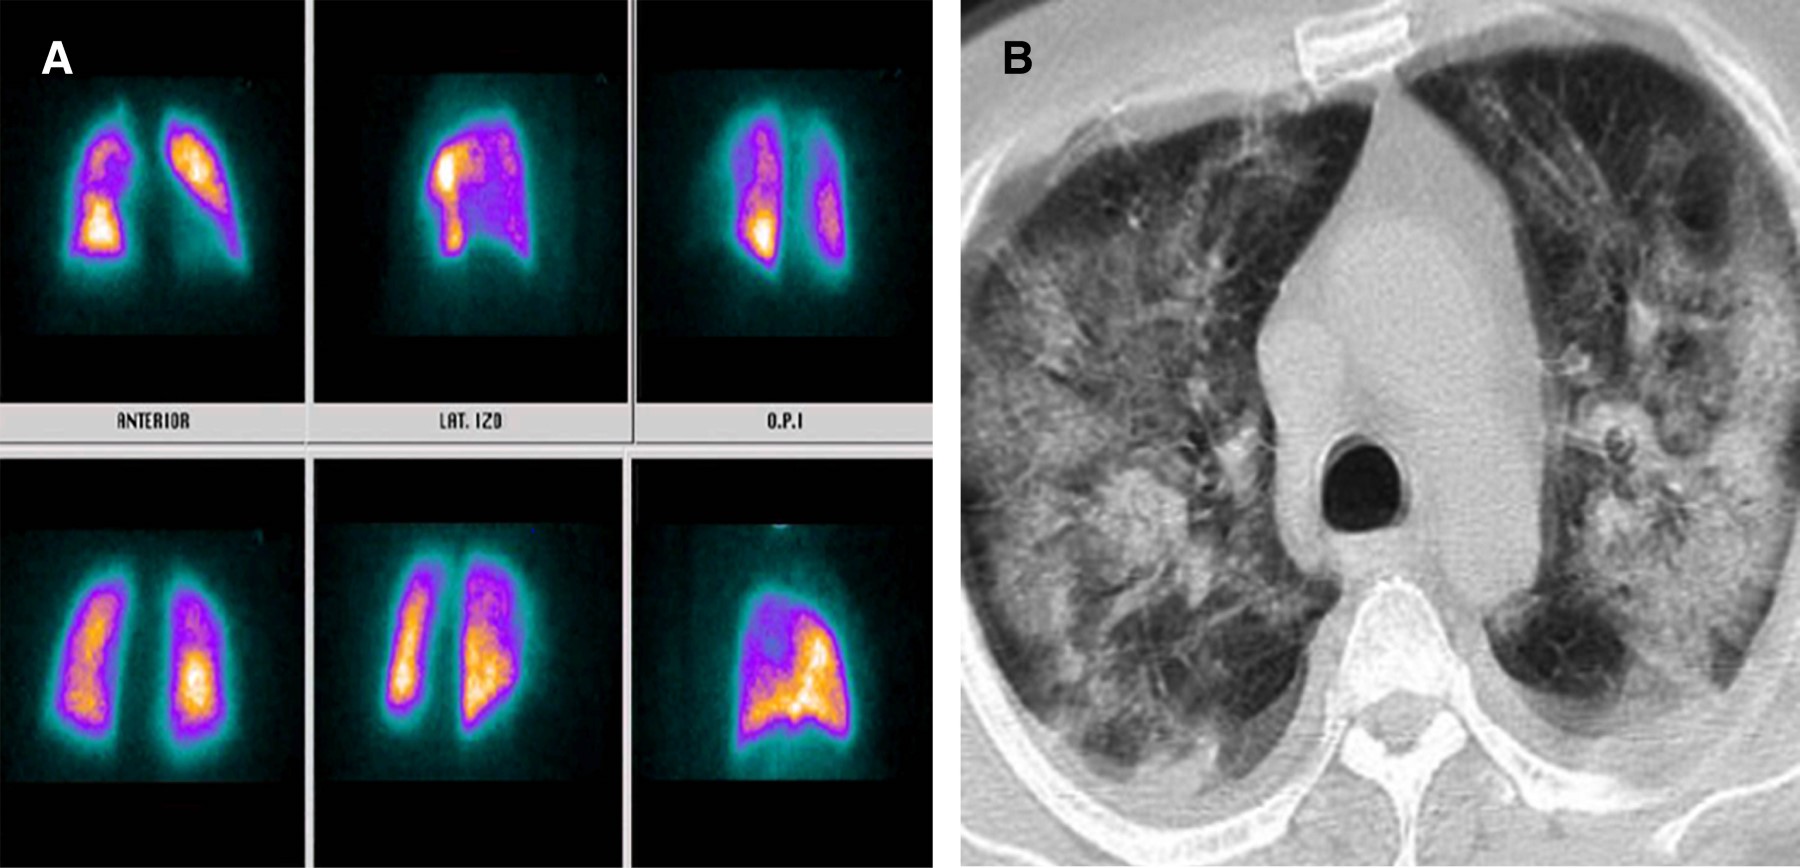

La infección por nuevo coronavirus es una entidad clínica altamente letal que trae consigo serias disfunciones celulares en primera línea de defensa, lo cual genera potentes mecanismos de hipercoagulabilidad mediados por reclutamiento de células inflamatorias.1 Uno de ellos direccionado por la disfunción del polimorfonuclear a partir del receptor 2 de enzima convertidora de angiotensina generado por la interacción de la fenilalanina ubicada en la porción 486 de la proteína de espiga del coronavirus, constituyéndose como el efecto más quimiotáctico existente, incluso superior al de la interleucina 8 (IL-8).2 A partir de esta situación, el reclutamiento del neutrófilo trae consigo la formación de una fina red inflamatoria inductora de integrinas denominadas NET (Neutrophil Extracellular Traps), produciendo activación de la vía intrínseca de la coagulación a partir del factor XII de Hageman. Adicionalmente, la muerte programada de dichas células, mediante la inducción de apoptosis, ocasiona liberación de histonas y restos de ADN, lo que precipita la formación de trombina.3,4 Por otro lado, la infección por nuevo coronavirus altera la respuesta del huésped al inóculo mediante modificación de los micro-ARN linfocitarios, lo que ocasiona disfunción del fagosoma natural en estadios de inmunocompetencia exacerbada o inmunosupresión manifiesta que a la postre desencadena estrés oxidativo, liberando grupos de proteínas de elevada movilidad (High Mobility Protein Box 1 [HMGB1]) y generando inflamación, coagulación y apoptosis.5 Pero, sin duda alguna, la linfopenia inducida por el coronavirus tipo 2 se constituye como el determinante más letal de trombosis mediante activación de la vía extrínseca e intrínseca de la coagulación, de la mano de un influjo descomunal de trombina. Se han identificado tres mecanismos de muerte celular programada en el linfocito de pacientes con la enfermedad por coronavirus del 2019 (COVID-19); uno de ellos es por activación del factor de transcripción nuclear y factor nuclear kappa beta, otra es por la activación del mitógeno p37 de la proteincinasa y la más deletérea mediante autofagocitosis determinante de un potente estado protrombótico.6 Con base en el conocimiento de los escenarios disfuncionales hematológicos durante la infección por nuevo coronavirus, se hace perentoria la predicción de enfermedad pulmonar tromboembólica, existiendo la duda razonable entre la prevención y la terapia antitrombótica, motivo por el cual la presencia de marcadores de actividad de fibrinolítica debe ser validada en tiempo presente y real. Teniendo en cuenta la mejor sensibilidad y especificidad disponible, las diferentes técnicas de enzimas líticas de inmunoensayo, hemaglutinación y látex deben someterse a consideración durante la estratificación diagnóstica.7,8 Una vez discriminados los pacientes con SARS-CoV-2 con pretest clínico medio para enfermedad pulmonar tromboembólica con reporte de dímero D por técnica de látex positivo y cuyos resultados de angio-TAC descartaron tromboembolia pulmonar (TEP); se les documentó, desde el punto de vista imagenológico, los defectos segmentarios de distribución vascular con morfología triangular de base externa y vértice interno por medicina nuclear, los cuales se correlacionaron muy de cerca con hallazgos en escanografías simples de tórax con atelectasias, efusión pleural y condensaciones, así mismo la presencia de alta probabilidad para TEP se validó por criterios de PISAPED (Figura 1, 2, 3, 4, 5, 6 y 7).9

Figura 3